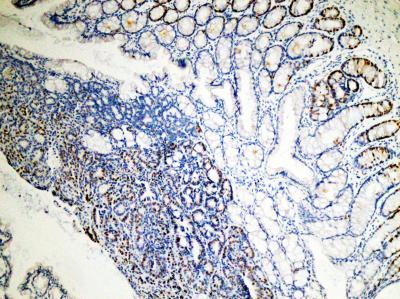

This shows cells proliferating in an intestinal tumor.

(Photo Credit: Sanford-Burnham Medical Research Institute)